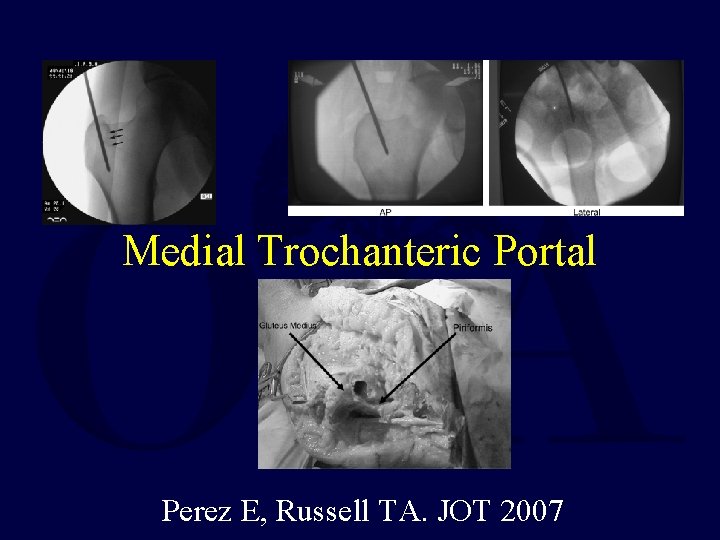

Medial Trochanteric Portal Perez E, Russell TA. JOT 2007